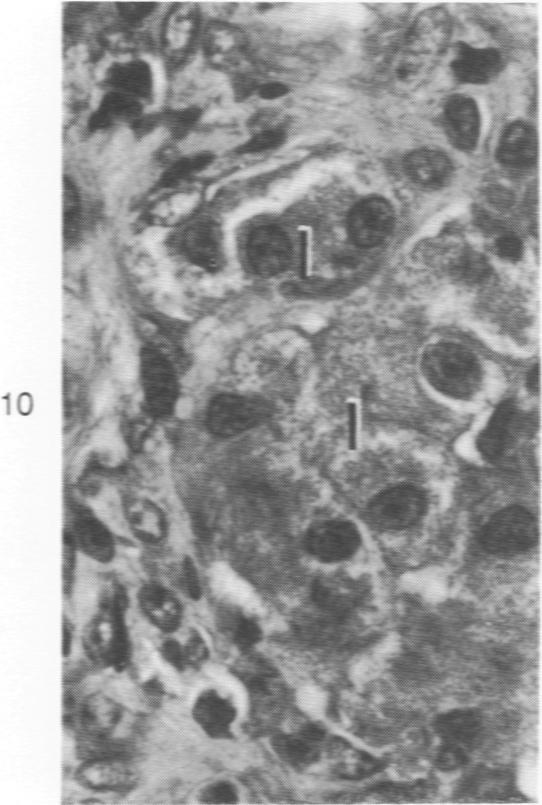

Syngeneic pancreatic islets transplanted into the liver or the spleen reverse streptozotocin-induced diabetes in the rat, but allogeneic islets function only briefly and are rejected. Shortly after transplantation, thrombi often form around transplanted tissue, particularly around nonislet tissue that contaminates islet preparations. These thrombi are a source of transient liver injury in recipients of intrahepatic grafts. A few days after transplantation, syngeneic islets injected into the portal vein are found at the periphery of portal tracts in direct contact with periportal hepatocytes, some of which become hypertrophied. Isografts remain situated in the portal tracts for prolonged periods without adverse effect on the surrounding liver. In contrast, allogeneic islets injected into the portal vein are infiltrated by small lymphocytes within 2 days of transplantation and are rapidly destroyed by the host. Syngeneic islets injected into the splenic pulp localize in the sinusoids and, 1 month or more after transplantation, are often surrounded by connective tissue or local collections of hemosiderin-laden macrophages. Allogeneic islets injected into the spleen are rejected with the same intensity and at approximately the same rate as allogeneic islets injected into the portal vein. Transplant rejection leaves no significant lasting morphologic effect on the host liver or spleen.

将同基因胰岛移植到肝脏或脾脏中可逆转链脲佐菌素诱导的大鼠糖尿病,但异基因胰岛仅能短暂发挥功能并被排斥。移植后不久,血栓常围绕移植组织形成,尤其是在污染胰岛制剂的非胰岛组织周围。这些血栓是肝内移植受体短暂性肝损伤的一个来源。移植几天后,注入门静脉的同基因胰岛位于门管区周边,与门周肝细胞直接接触,其中一些肝细胞会肥大。同基因移植胰岛可长时间位于门管区,而对周围肝脏无不良影响。相比之下,注入门静脉的异基因胰岛在移植后2天内就会被小淋巴细胞浸润,并迅速被宿主破坏。注入脾髓的同基因胰岛定位于血窦,移植1个月或更长时间后,常被结缔组织或含铁血黄素巨噬细胞局部聚集所包围。注入脾脏的异基因胰岛与注入门静脉的异基因胰岛以相同强度、大致相同速率被排斥。移植排斥对宿主肝脏或脾脏没有显著的持久形态学影响。